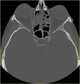

Acute sinusitis

Sinusitis, also known as rhinosinusitis, is inflammation of the mucous membranes that line the sinuses resulting in symptoms that may include thick nasal mucus, a plugged nose, and facial pain. Other signs and symptoms may include fever, headaches, a poor sense of smell, sore throat, and a cough. [Source: Wikipedia ]